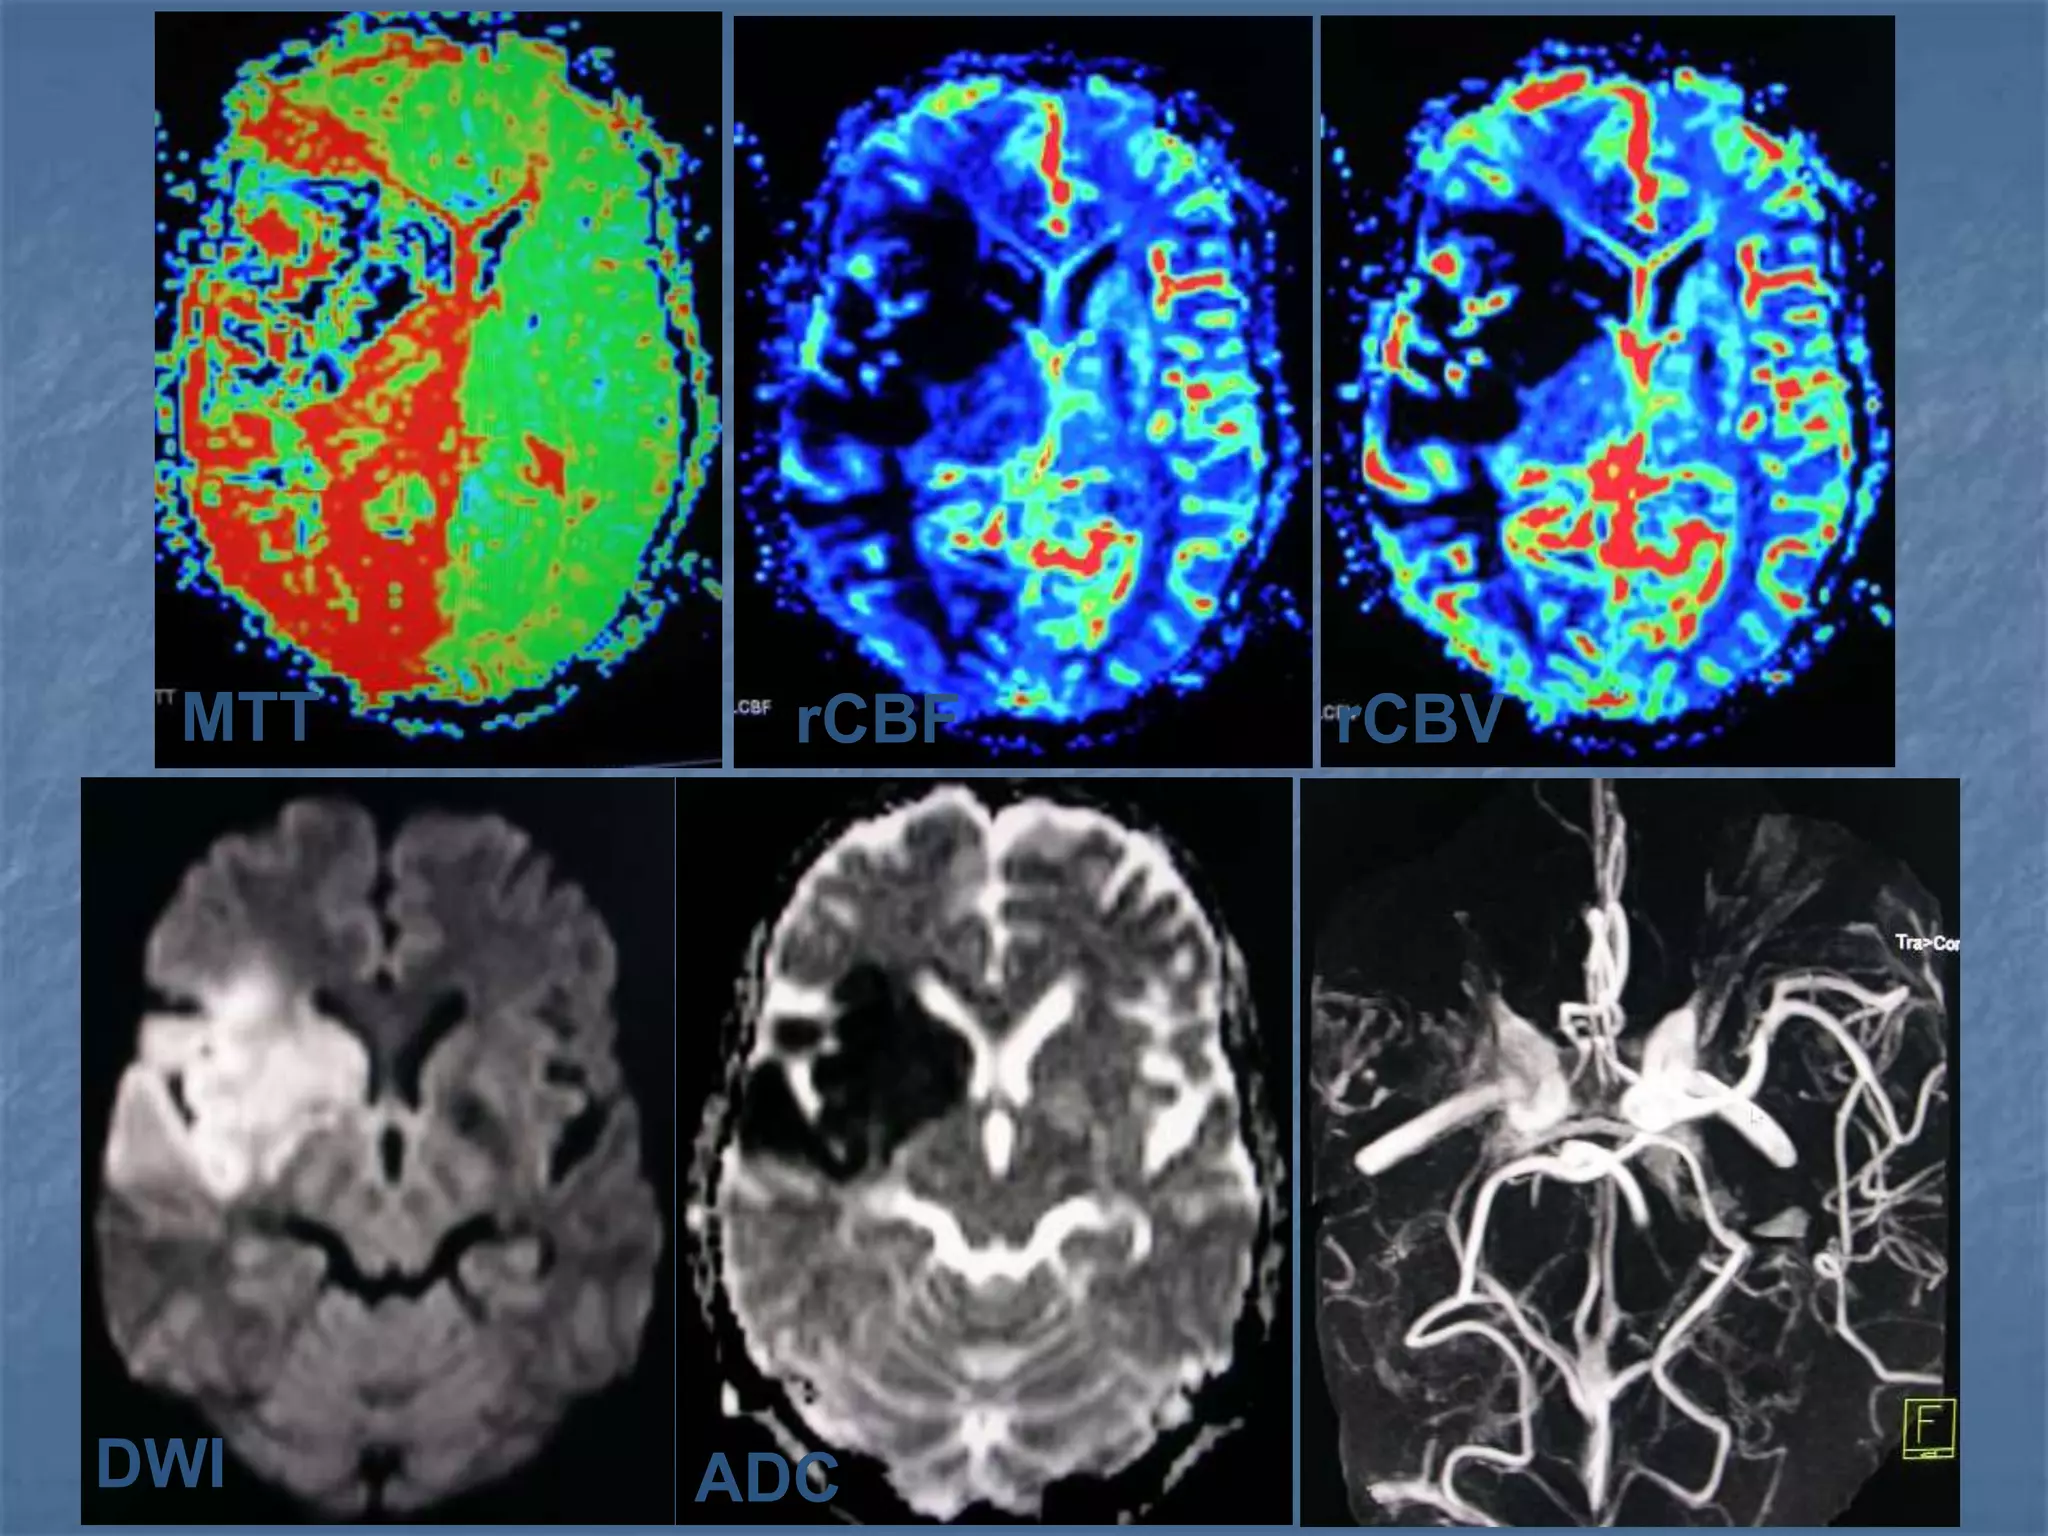

CT / MR Perfusion imaging

 Concentrates on the assessment of mean

transit time (MTT), relative cerebral blood

volume (RCBV) and derived relative cerebral

blood flow. RCBF = MTT / RCBV

 Prolonged MTT is the earliest & most consistent

sign of impaired perfusion.

 In addition to this, there is a simultaneous drop

in RCBV indicating tissue at risk for infarction.

MRI in Hyperacute Stroke

 DWI – Infarct core

 FLAIR - SAH , Parenchymal changes

 T2* GRE – Intracranial hemorrhage

 PWI – Perfusion deficit

 MRA – Vessel occlusion

Combined MR Perfusion & Diffusion

Imaging

 In hyperacute stage, larger abnormality is

noted on the perfusion images than on

diffusion weighted images. This diffusion

perfusion mismatch is the ischemic

penumbra. This is the tissue at risk which

would benefit from thrombolysis.